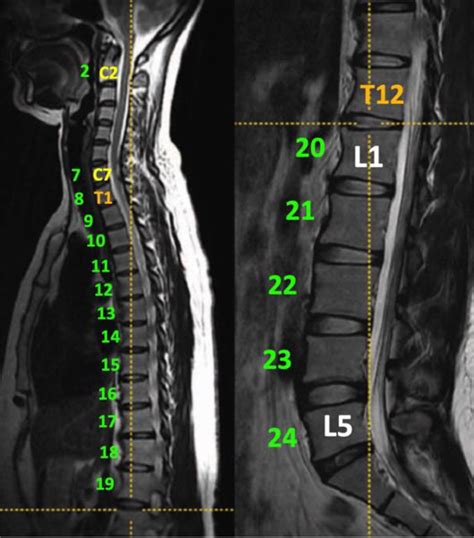

Diagnosing Lumbosacral Transitional Vertebrae

Diagnosing LSTV typically involves a combination of imaging techniques and clinical evaluation. The most common methods include:

• MRI Scans: Provide information about the soft tissues and can help assess the impact of LSTV on the spinal cord and nerves.

• lumbosacral transitional vertebrae mri